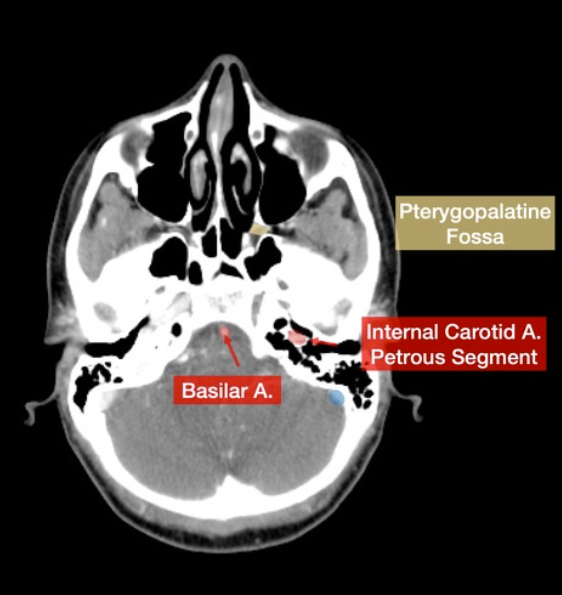

Please label the internal carotid artery (ICA)